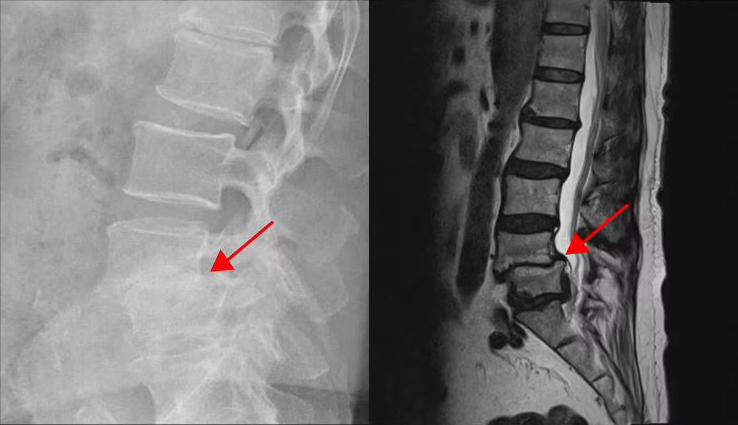

다음은 두 번째 환자분입니다. 이 환자분은 4-5번 오른쪽에 심한 추간공협착증이 있는 상태였고, 2단계의 전방전위증이 있으셨습니다. 이런 심한 협착으로 인해 다리에 마비가 와서 거의 걷지 못하셨습니다. 신경주사도 많이 맞아봤지만 전혀 효과를 보지 못해서 결국 허리협착증 수술을 결심하고 대학병원 등 9군데의 병원에서 진료를 받았지만, 어려운 수술이라고 하면서 병원마다 제시하는 수술방법이 달라 큰 혼란을 겪으셨습니다.